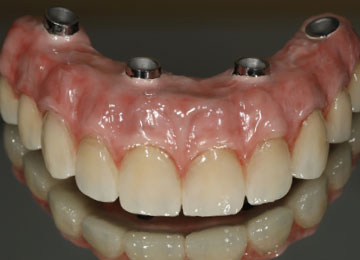

Имплантация зубов: фото «До» и «После»

Фото ПОСЛЕ

Наведите для просмотра

All-on-4